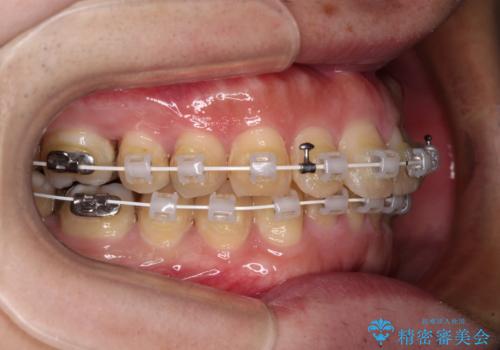

- 矯正装置

- 審美装置

- 深い咬み合わせによる食いしばりで、顎関節や頭が痛むことがあるとのことで来院された患者様です。

歯ぎしりができないくらい強い食いしばりの咬合状態であったため、奥歯の歯軸を起き上がらせることで咬合を挙上させ、歯ぎしりができるようにしていくこととしました。

インビザラインでの矯正治療も可能でしたが、自己管理の煩わしさを嫌ってワイヤー装置による矯正治療を行うこととしました。

下顎が左側にずれているため、上下正中は最大限合わせられるところまで合わせるゴールとなりました。